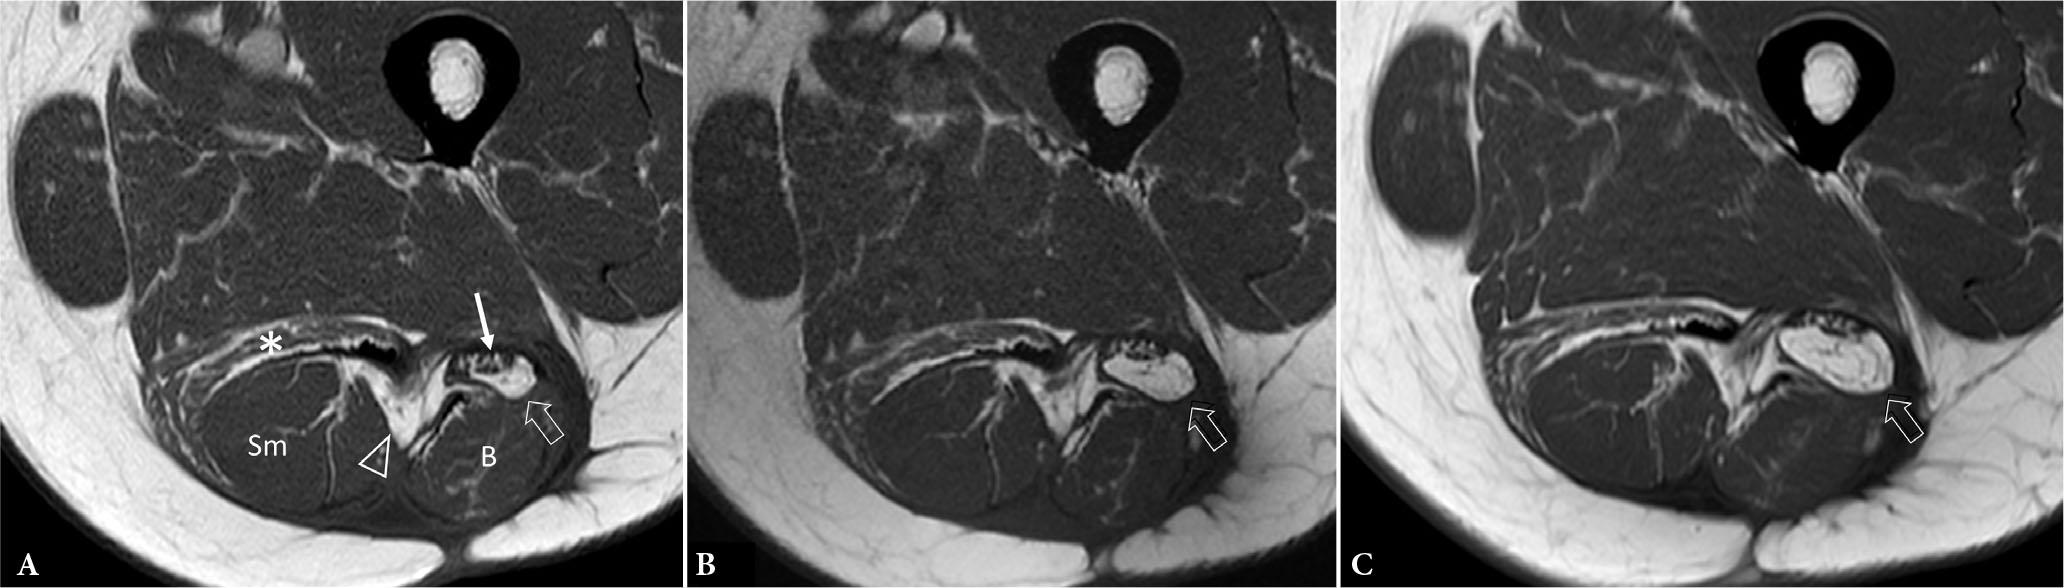

Fig. 16.

63-year-old male following resection of well-differentiated liposarcoma posterior aspect thigh. T1-weighted (T1W) axial MR images thigh A. nine months post-operation shows severe semitendinosus muscle atrophy (*), increased intermuscular fat (arrowhead) between semimembranosus (Sm) and long head biceps femoris B. muscles as well a fatty mass (volume 1.6 ml) (open arrow) posterior to sciatic nerve (arrow). B. Fourteen months post-operation, the fatty mass posterior to sciatic nerve had increased by 143% (volume 3.9 ml). C. Nineteen months post-operation, the fatty mass posterior to sciatic nerve had further increased by another 130% (volume 9 ml), compatible with liposarcoma recurrence. MRI is generally better than US for post-operative surveillance. Volume, rather than linear, measurements provide a more ready appreciation of changing tumor size. In this case, volume measurements were made by formulaic estimation (length × width × depth × 0.52) rather than tumor segmentation